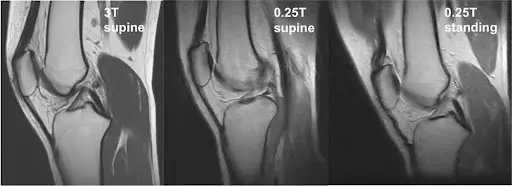

Real-time, weight-bearing and natural-position imaging captures how your body truly functions, enabling precise evaluation and guiding effective treatment plans for faster recovery.

Pain often appears when standing or moving, not when lying flat. This helps detect real-life problems.

• Doctors see how joints behave under real conditions

• Subtle problems become visible

• Treatment decisions become clearer

Yes. Upright MRI provides highly accurate diagnostic images, and in some cases can even show issues more clearly because it captures the body in natural, weight-bearing positions.